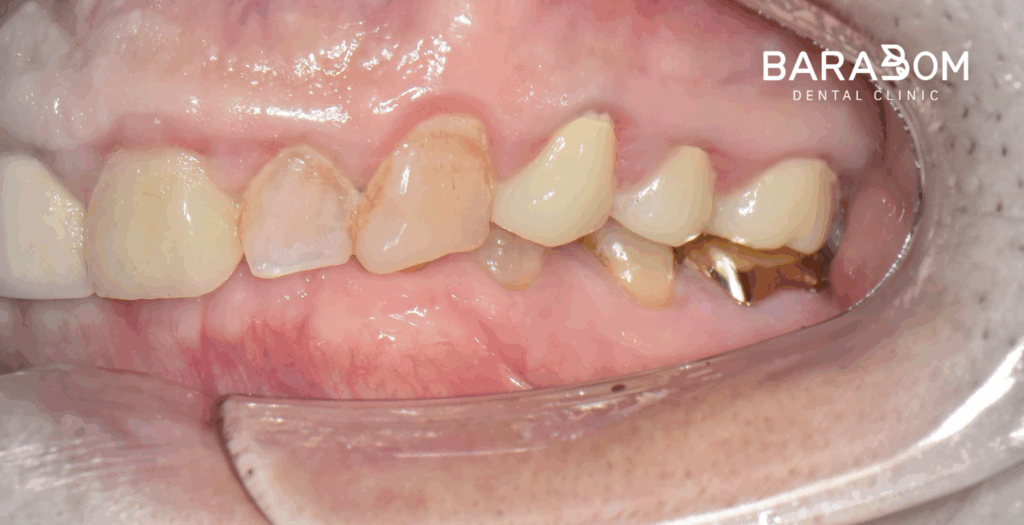

준비한 사진을 보시면, 윗니가 아랫니를 일절 다 덮을 정도로 깊게 물리고 있습니다.

더불어 교합력이 센 탓에 교모가 꽤 심하게 진행되었습니다.

대개 교모로 인하여 수직 고경이 상실된 케이스를 보면 치관의 길이가 매우 짧습니다. 이런 상태에서 크라운을 씌우게 되면 당연히 안정을 얻기 어렵습니다.

그럼 자주 보철이 탈락하게 되어 불편으로 이어질 수 밖에 없는데, 현재 하악 앞니 뿐만 아니라 어금니도 치아 머리의 길이가 짧은 상태였습니다. 하악 절치부 치관 길이가 매우 짧으며, 상악 절치 구개부와 간격이 불과 2mm 이내였습니다. 현재 상태로써 새로운 보철을 제작하긴 어렵다 판단되고 있습니다.